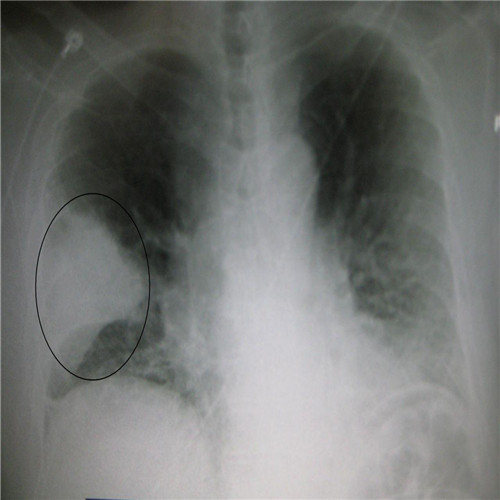

呼吸道感染胸腔積液胸片下觀察